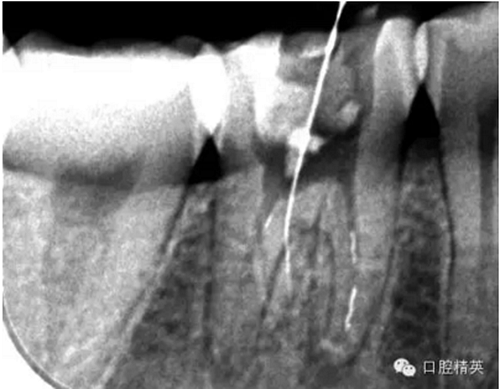

這個(gè)病例是我準(zhǔn)備分根的病例,保留近中根,曾在外院做過(guò)干尸長(zhǎng)達(dá)數(shù)十年。8號(hào)挫疏通時(shí)近舌根堵,近頰未找到。在這個(gè)病例中首先要知道是為什么根管難以疏通,首先是長(zhǎng)時(shí)間的干尸,和患者年紀(jì)較大根管逐漸變窄,根管道路可能會(huì)出現(xiàn)堵塞,在這張病例中我能知道的是稍有不慎就會(huì)形成臺(tái)階,從而導(dǎo)致根管堵塞加重,更加難以疏通。